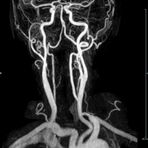

- MR-Angiografie ohne Kontrastmittel

- Time of Flight (TOF)-Angiographie

- Phasenkontrastangiographie (PCA). Geeignet zur Quantifizierung Stenose-/Insuffizienzgrad z.B. bei Herzklappen, falls echokardiographisch die Untersuchungsbedingungen eingeschränkt sind.

Je nach Fragestellung und Körperregion Gefäßdarstellung ohne Kontrastmittel bei Kontrastmittelunverträglichkeit oder terminaler Niereninsuffizienz möglich.

- MR-Angiographie mit Kontrastmittel

- Erfassung arterieller und venöser Gefäße/Bypässe aller Körperregionen mit 3D-Rekonstruktion